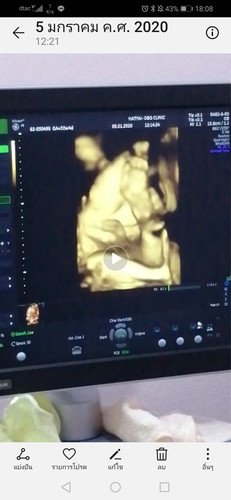

ท่านอนในท้อง

น้องนอนท่านี้ปกติไหมคับ เอาขาขึ้นมาอยู่ที่หน้า